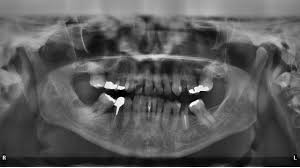

Orthodontic Imaging Solutions Handheld Dental X Ray Systems Amalgam Fillings Dental Dental Fillings